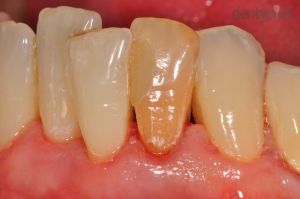

Ínyvisszahúzódás kezelése

Parodontológiai kezeléseink közé tartozik a visszahúzódott fogíny, más néven ínyrecesszió ellátása is. A fogíny a beavatkozást követően tökéletesen egészséges és ismét képes rá, hogy megvédje a fogat az esetleges károsodásoktól vagy a hideg-meleg ételek, italok okozta ingerektől!

Recessziófedés: Dr. Szvoboda Balázs

1) Kiindulási helyzet

2) Ínyrecesszió fedése

Többszörös ínyvisszahúzódás kezelése

Páciensünk felső szemfogáról erősen visszahúzódott a fogíny, melynek következtében a fognyak szabaddá vált, ami fogérzékenységhez, fognyaki kopáshoz-, és szuvasodáshoz vezethet. Dr. Molnár Bálint parodontológus szakorvos ínyplasztika segítségével állította helyre a visszahúzódott fogínyt.

Recessziófedés: Dr. Molnár Bálint

2) Többszörös ínyvisszahúzódás kezelése után